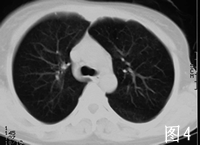

2001年7月患者无明显诱因出现间断性发热,体温最高达38℃,无伴随症状,给予青霉素等治疗可好转。2002年3月底患者再次出现发热,体温在38℃左右,伴畏寒、咳嗽、咳白痰和胸闷气短,血常规正常,先后给予多种抗生素治疗无效。4月底在我院就诊时发现人免疫缺陷病毒抗体HIV Ab初筛和确证试验均阳性,CD4+ T淋巴细胞仅14/μk,X线胸片和胸部CT显示双肺弥漫性片状浸润阴影(见图1、2)。确诊AIDSC3期,结合患者胸部影像学表现和进行性呼吸困难,考虑卡氏肺孢子虫(PCP)肺炎可能性大,于4月29日开始给予复方磺胺甲 唑(复方新诺明,SMZCO2片,每日4次。患者自发病以来,食欲明显减退,体重下降10 kg。

患者入院后在坚持SMZCO治疗的同时,为促进肺部炎症迅速吸收,短期给予大剂量泼尼松治疗泼尼松60 mg/d,每3~4日减20 mg,2周内停用,患者呼吸困难迅速缓解,血氧饱和度由90%上升到99%。2周后SMZCO减为2片/d维持治疗。2周后复查X线胸片和胸部CT(见图3、4),见双肺的阴影明显吸收,但右上肺病灶没有吸收。考虑患者合并感染肺结核,给予异烟肼、乙胺丁醇和吡嗪酰胺治疗。从5月10日开始给予患者叠氮胸苷、拉米夫定和印地那韦进行高效抗逆转录病毒治疗HAART。